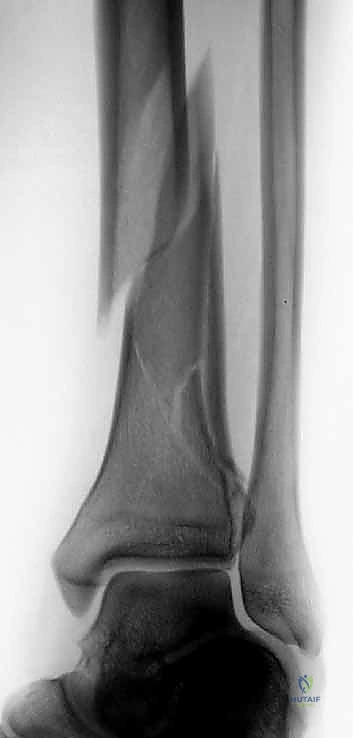

1. التصوير بالأشعة السينية التقليدية (X-Rays)

يتم أخذ صور من ثلاث زوايا (أمامية خلفية AP، جانبية Lateral، ومورتيس Mortise). تعطي هذه الصور فكرة عامة عن نمط الكسر، قصر الساق، ومدى انزياح العظام.

في حوالي 90% من حالات كسور البيلون عالية الطاقة، نجد كسرًا مصاحبًا في عظم الشظية. هذا ليس مجرد تفصيل جانبي؛ بل هو مؤشر حاسم على مقدار الطاقة المدمرة التي امتصها الطرف، ويلعب دورًا محوريًا في استراتيجية الأستاذ الدكتور محمد هطيف الجراحية، حيث غالبًا ما يتم تثبيت الشظية أولاً كخطوة أساسية لاستعادة الطول التشريحي للطرف وضبط الدوران الصحيح قبل الانتقال للتعامل مع المفصل المفتت.

- تشوه واضح في الكاحل: قد تبدو القدم ملتوية للخارج أو للداخل بشكل غير طبيعي، أو تبدو الساق أقصر من الطبيعي بسبب انضغاط العظام.